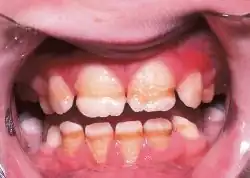

Enamel hypoplasia is a defect of the teeth in which the enamel is deficient in quantity,[1] caused by defective enamel matrix formation during enamel development, as a result of inherited and acquired systemic condition(s). It can be identified as missing tooth structure and may manifest as pits or grooves in the crown of the affected teeth, and in extreme cases, some portions of the crown of the tooth may have no enamel, exposing the dentin.[2] It may be generalized across the dentition or localized to a few teeth. Defects are categorized by shape or location. Common categories are pit-form, plane-form, linear-form, and localised enamel hypoplasia.[3][4][5] Hypoplastic lesions are found in areas of the teeth where the enamel was being actively formed during a systemic or local disturbance. Since the formation of enamel extends over a long period of time, defects may be confined to one well-defined area of the affected teeth. Knowledge of chronological development of deciduous and permanent teeth makes it possible to determine the approximate time at which the developmental disturbance occurred.[6] Enamel hypoplasia varies substantially among populations and can be used to infer health and behavioural impacts from the past. Defects have also been found in a variety of non-human animals.[7][8][9]

Irreversible enamel defects caused by an untreated celiac disease. They may be the only clue to its diagnosis, even in absence of gastrointestinal symptoms, but are often confused with fluorosis, tetracycline discoloration, or other causes.[10][11][12] The National Institutes of Health include a dental exam in the diagnostic protocol of celiac disease.[10]